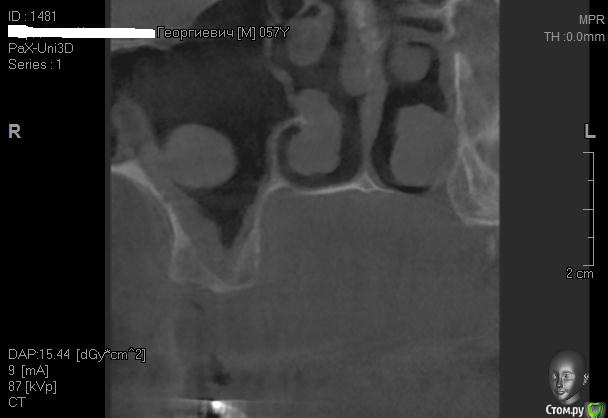

Kostoprav Опубликовано 26 апреля, 2015 Поделиться Опубликовано 26 апреля, 2015 Всем доброго времени суток коллеги!Проблема в следующем- высокая септа и мукоцеле на медиальной стенке пазухи.Мой план: сделать два окна в пазуху по обе стороны от перегородки, аккуратно попробовать отслоить слизистую и если получиться не порвать ее установить два болта не трогая кисту. В случае тотального разрыва мембраны спилить перегородку, убрать мукоцеле, зашить пазуху и повторно пойти на синуслифт через 2 месяца.Хотелось бы услышать Ваши варианты дорогие коллеги. 1 Ссылка на комментарий

Alexey Doc Опубликовано 26 апреля, 2015 Поделиться Опубликовано 26 апреля, 2015 Покажите пожалуйста соустье справа. На этих срезах видно только слева Ссылка на комментарий

Kostoprav Опубликовано 26 апреля, 2015 Автор Поделиться Опубликовано 26 апреля, 2015 (изменено) соустье работает Изменено 26 апреля, 2015 пользователем Kostoprav Ссылка на комментарий